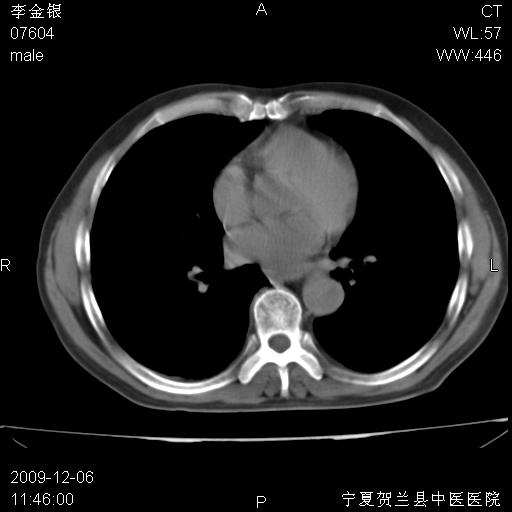

该病人 ,男,62岁,主因咳痰带血两天

考虑右肺中心型肺癌伴阻塞性肺炎及右肺门淋巴结转移,建议纤维支气管镜进一步检查。

右肺上叶后段支气管阻塞,右上肺门占位,相应肺段阻塞性肺炎,右肺门有淋巴结肿大。诊断右肺上叶中心型肺癌,阻塞性肺肺炎、右肺门淋巴结转移。

右肺中心型肺癌伴阻塞性肺炎及右肺门与纵膈淋巴结转移很典型,可纤维支气管镜进一步检查

考虑右侧中央型肺癌伴右肺上叶后段阻塞性炎症、肺不张、右肺门和纵隔淋巴结肿大。

右肺上叶中心型肺癌,阻塞性肺炎、右肺门和纵隔淋巴结转移。